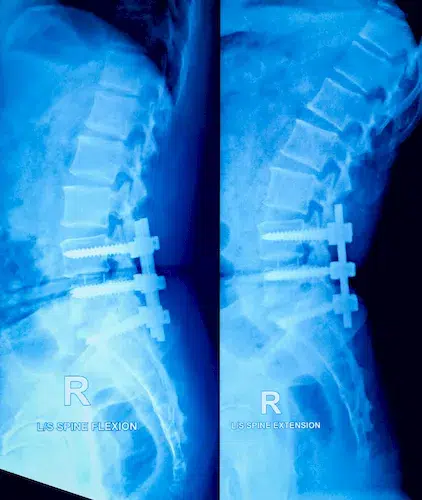

| ▸ | Röntgen Erkennung von Knochenbrüchen (zuverlässige Ergebnisse erst im späteren Krankheitsverlauf – neue, starke Rückenschmerzen; chronische Rückenschmerzen unbekannter Ursache; hohes Lebensalter; niedrige Knochendichte; mehrere, alte Brüche; Größenverlust von > 5 cm seit 25. Lebensjahr und > 2 cm bei Kontrolluntersuchungen) |

Röntgenaufnahmen von verschiedenen Knochenbrüchen bei Osteoporose

Diese Diagnostikmethoden kombiniert sind von großer Bedeutung, um individuelle Risikoprofile zu erstellen und eine präzise Behandlung einzuleiten. Eine frühzeitige Untersuchung ermöglicht es Ihnen, gezielt Maßnahmen zu ergreifen und so die Stabilität Ihres Knochengerüsts langfristig zu sichern.